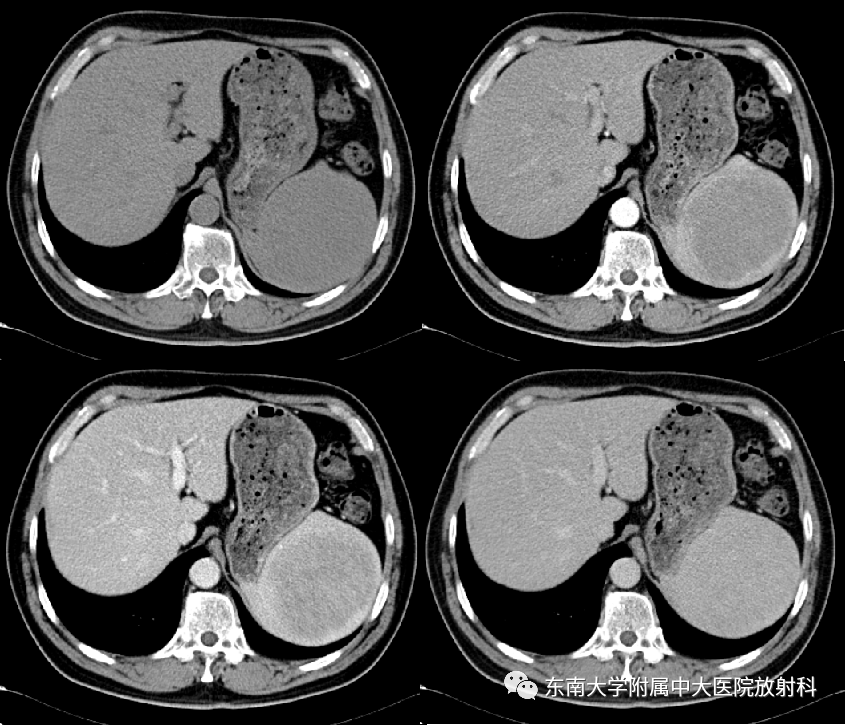

•女,48岁

•主诉:体检发现脾脏占位8天

•患者8天前于外院体检,查腹部彩超提示脾脏实性肿块

•男,55岁

•主诉:体检发现脾脏占位一周